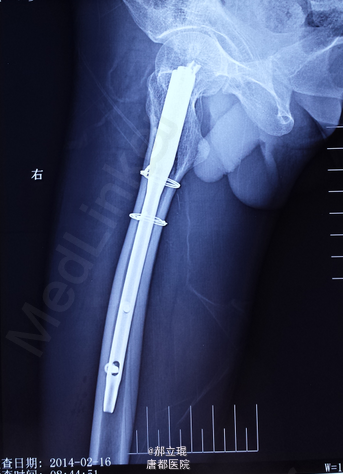

髓内钉

拍片,化验,X光片提示骨折。

做髓内钉手术处理。